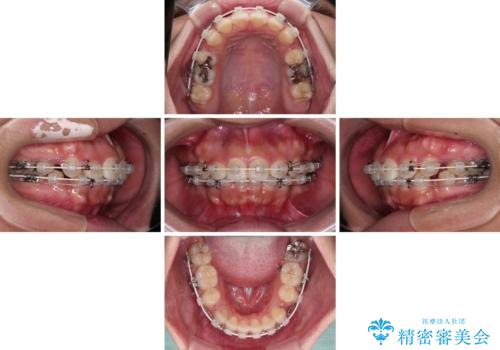

急速拡大とワイヤー抜歯矯正で唇を閉じやすく

デコボコと口元の突出感が認められたため、上下左右の第1小臼歯4本を抜歯してのワイヤー矯正を行うこととしました。

上顎歯列の横幅が狭く、下顎大臼歯の歯軸が舌側に倒れていたため、急速拡大装置により上顎骨を側方に拡大し、咬み合わせを改善することとしました。

上顎歯列幅を拡大したことで、デコボコを容易に解消することができるようになったため、抜歯により得られたスペースを口元の突出感改善に利用することができました。